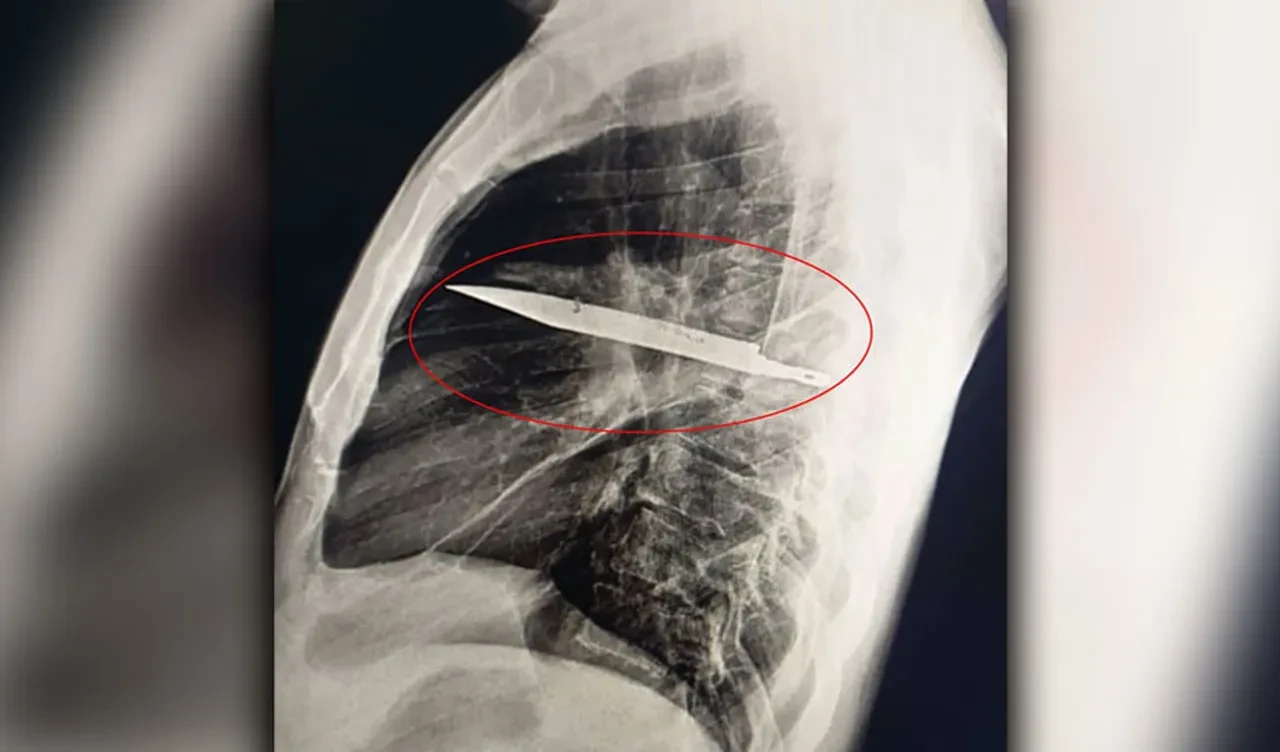

Doktorlar, röntgen çekilmesini istedi ve ardından büyük bir şok yaşandı. Adamın göğsünde bir bıçak olduğu ortaya çıktı. Hasta, seneler önce bir kavga esnasında, sırtından, göğsünden ve karnından yaralandığını, tedavi gördüğünü söyledi. O zamandan bu zamana kadar ise herhangi bir sağlık sorunu yaşamadığını söyledi.

Doktorlar, tedavi sırasında bıçağın unutulmuş olabileceğini, iltihap yapmasıyla beraber ortaya çıktığını ifade etti. The Sun'ın haberine göre, bıçak, sağ kürek kemiğinden girip hayati organlara zarar vermeden göğüste kaldı.